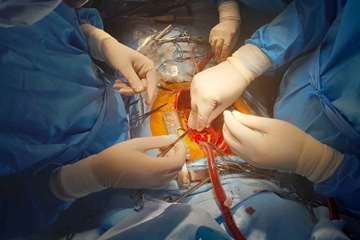

برای نخستینبار در بیمارستان فیروزآبادی؛ انجام موفق عمل جراحی قلب باز «بنتال»

برای نخستینبار در بیمارستان فیروزآبادی؛ انجام موفق عمل جراحی قلب باز «بنتال»

در این عمل سنگین که با تلاش تیم جراحی قلب بیمارستان فیروزآبادی انجام گرفت، دریچه آئورت بیمار با دریچه فلزی جایگزین شد و رگ آئورت صعودی نیز با استفاده از گرافت مصنوعی تعویض گردید.عمل جراحی بنتال از جمله عملهای فوقتخصصی و پرریسک قلب باز است که تنها در مراکز معدودی در کشور انجام میشود. خوشبختانه این عمل در بیمارستان فیروزآبادی با موفقیت کامل و حال عمومی مساعد بیمار پایان یافت.

با انجام این جراحی، بیمارستان فیروزآبادی توانست گامی مهم در مسیر ارتقای توان تخصصی و جراحیهای پیشرفته قلب و عروق بردارد و نام خود را در فهرست معدود مراکزی قرار دهد که قادر به انجام اینگونه اعمال فوقتخصصی هستند.